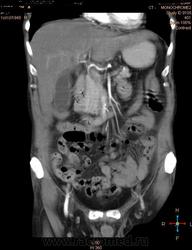

Здравствуйте, коллеги.Помогите разобраться.Пациент 1949 г беспокоять боли в животе , отсутствие аппетита, похудание .За неделю пожелтел, ослаблен.Нужно исключит кацер головки подж.железы.Анализы сегодня сдал еще не готовы.УЗИ зак увеличение л\узлов у ворот печени.Образов головки подж.железы ?На КТ жировой гепатоз.вроде головка подж железы не увеличены.

Мне надо исключить или поставить образование головки подж.железы.Хирурги ждут заключение, хотять оперировать.

А про билиарную гипертензию на УЗИ и КТ ничего не говорится?

Даже если вы пропустили малый рак панкреас, пациент умер не из-за него - желтуха не механическая, а, вероятней, паренхиматозная.